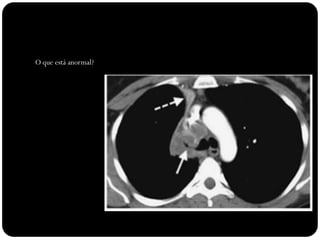

Vias aéreas

O que está anormal?

Brônquio traqueal

aberrante